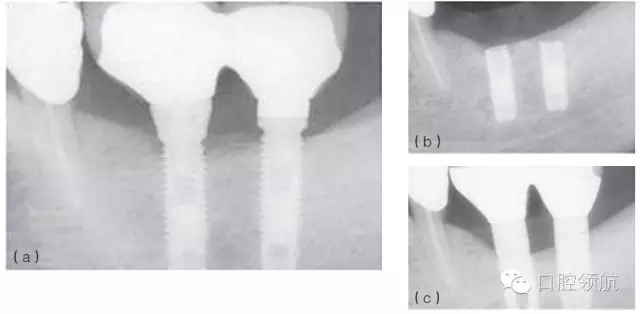

例如,在發(fā)生率低的種植體折斷病例中,感染和創(chuàng)傷經(jīng)常同時存在,或相繼發(fā)生。感染引起的種植體周骨喪失(種植體周圍炎)也可能導致種植體折斷。過載或創(chuàng)傷則是種植體折斷的第二個因素,種植體折斷的高度常常與骨-種植體的接觸水平相一致(圖6.4a~c)。也可相反,種植體周感染繼發(fā)于咬合創(chuàng)傷,導致種植體不能形成骨結(jié)合而失敗。(圖6.5a~c)

圖6.4 (a)18號、19號位點種植體出現(xiàn)邊緣骨吸收。(b)2年后出現(xiàn)折斷。(c)拔除了舊的種植體,新的種植體植入并進行修復。